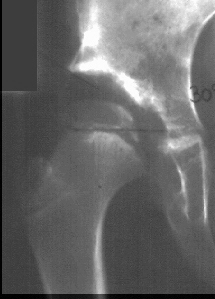

Following traction, open reduction was repeated, with satisfactory results;

however subsequent radiographs show an irregular pattern of growth with

a tendency for subluxation even though it was treated part time in an abduction

brace.

At 5 + 8 years of age

,

a clinical diagnosis of Charcot-Marie-Tooth disease was made, and Shelf

arthroplasty was performed to increase the femoral head coverage.